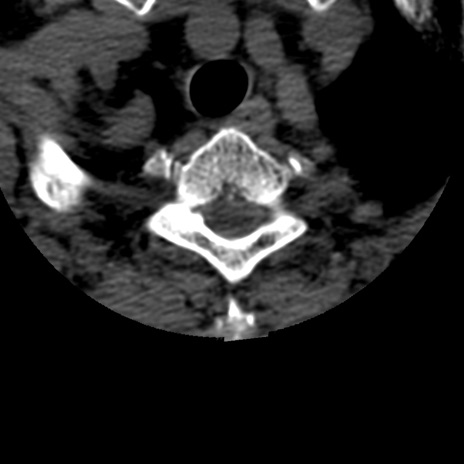

症例50 頚椎CT(横断像)

頚椎CT